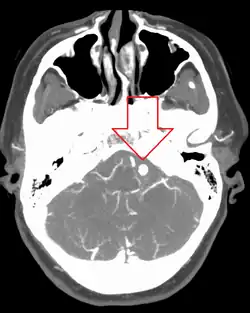

Diagnosis of a ruptured cerebral aneurysm is commonly made by finding signs of subarachnoid hemorrhage on a computed tomography (CT) scan. If the CT scan is negative but a ruptured aneurysm is still suspected based on clinical findings, a lumbar puncture can be performed to detect blood in the cerebrospinal fluid. Computed tomography angiography (CTA) is an alternative to traditional angiography and can be performed without the need for arterial catheterization. This test combines a regular CT scan with a contrast dye injected into a vein. Once the dye is injected into a vein, it travels to the cerebral arteries, and images are created using a CT scan. These images show exactly how blood flows into the brain arteries.[39]